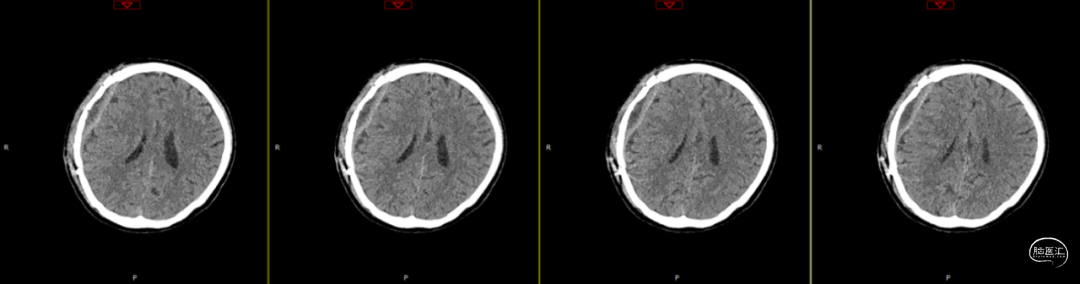

第2次手术后第17天,行颅脑CT检查(如上图),科室讨论仍建议去骨瓣清创,但患者情绪波动明显,拒绝去骨瓣;经协商后行硬膜外脓肿置管引流术。术中根据术前规划,切开颞顶部部分头皮,高速磨钻经骨缘与骨瓣之间磨出骨孔及骨槽,可见骨缘硬脑膜增生,深部硬膜增厚,并伴有灰黄色粘稠脓性液体流出,无明显异味,使用无菌注射器收集脓液约7ml,备细菌培养等检查;置引流管于硬膜外,骨瓣下,反复使用温生理盐水冲洗至水清晰,接负压吸引,及引流袋;术后继续使用万古霉素及美罗培南联合抗炎治疗。术后每日使用万古霉素溶液冲洗硬膜外腔1次。

第3次术后第9天复查颅脑CT(如上图)。

第3次术后16天,复查颅脑MRI(如上图),硬膜外及皮下异常信号较前明显减少,负压引流管引流不明显,拔除负压引流管,继续使用头孢曲松+多西环素口服联合抗炎治疗。

第3次术后23天,拔管后7天复查颅脑(如上图)。

第3次手术后49天,出院后2周复查颅脑CT情况(如上图),刀口愈合正常,患者回归日常生活、学习。